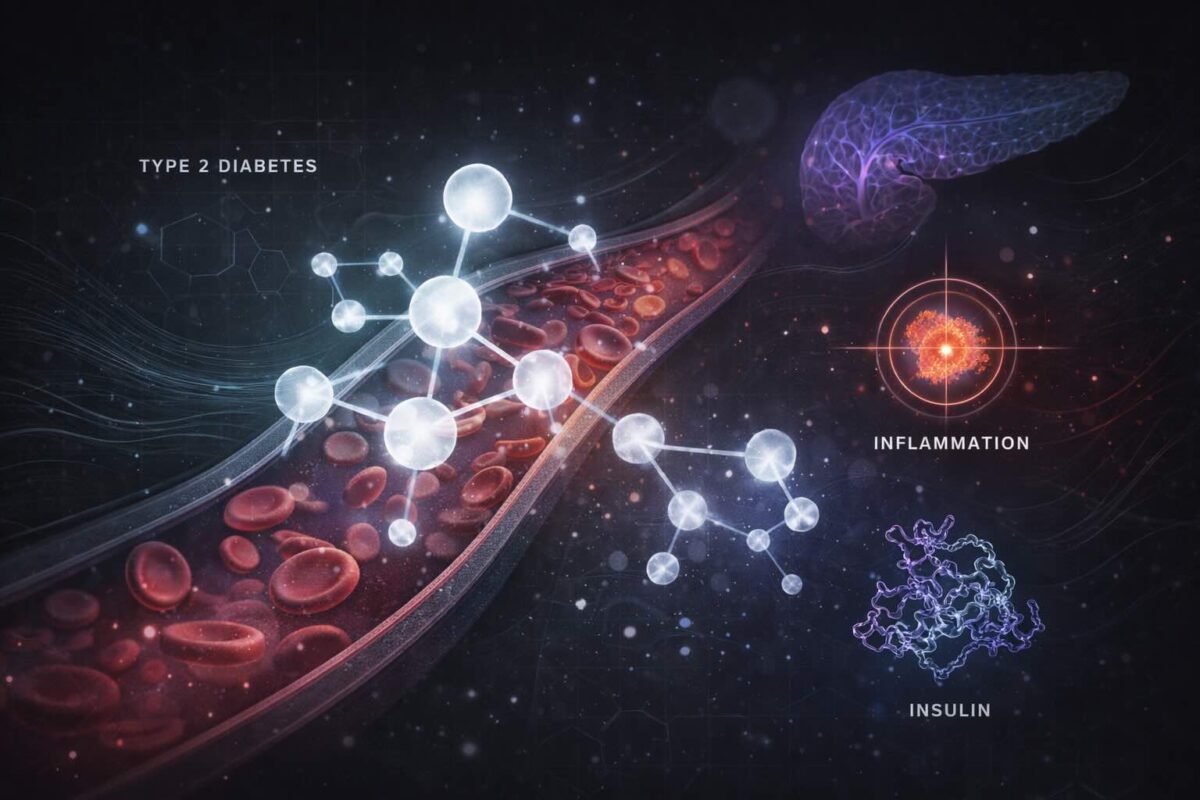

How Peptide-Based Therapies Like Exenatide Target Insulin Resistance and Inflammation in Type 2 Diabetes